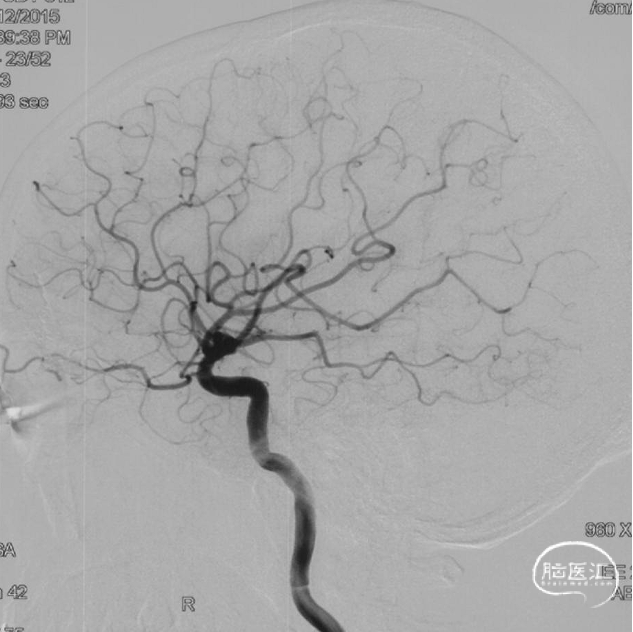

术前造影

双侧颈内动脉正侧位造影见前颅窝底硬脑膜动静脉瘘,双侧筛前动脉、筛后动脉向瘘口供血,通过皮层静脉向上矢状窦引流。

双侧颈外动脉正侧位造影见镰前动脉向瘘口供血。

左侧椎动脉正侧位造影未见明显异常。

前颅窝底DAVF,由镰前动脉、双侧筛前、筛后动脉参与供血,通过皮层静脉向上矢状窦引流,引流静脉伴有瘤样扩张,Cognard IV型、Borden III型。由于脑膜中动脉-镰前动脉路径较为迂曲,超选困难,引流静脉迂曲扩张,预计到达瘘口起始端存在困难,决定经眼动脉-筛前动脉栓塞。